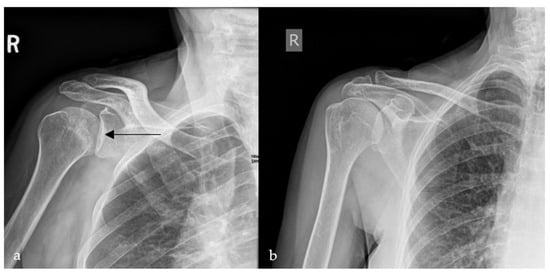

2.4. Loss of Half-Moon Overlap Sign

- Gor, D. The Trough Line Sign. Radiology 2002, 224, 485–486. [Google Scholar] [CrossRef] [PubMed]

- Sanders, T.; Jersey, S. Conventional Radiography of the Shoulder. Semin. Roentgenol. 2005, 40, 207–222. [Google Scholar] [CrossRef]